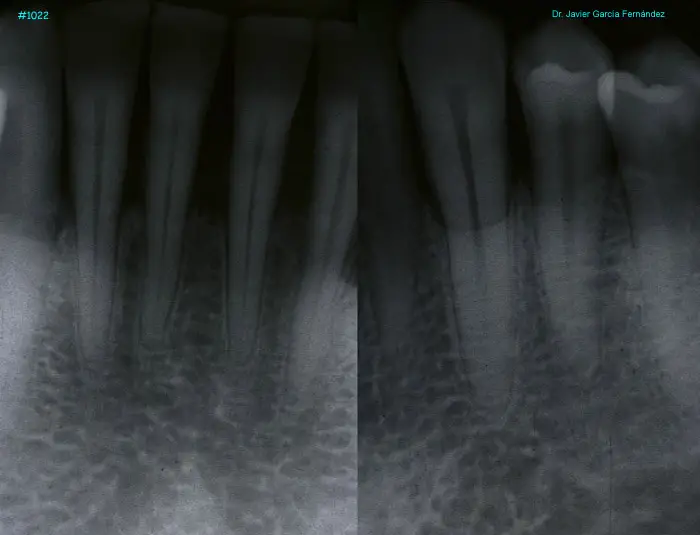

Atlas of Surgical Techniques in Periodontics. Chapter III. Atlas de Técnicas Quirúrgicas en Periodoncia

image398